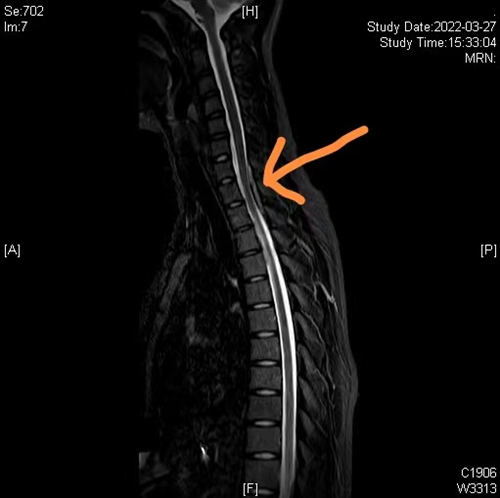

术前颈胸椎磁共振(黄色箭头提示硬膜外血肿,脊髓受压)